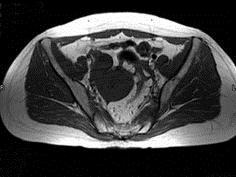

问题 女性,46岁,无任何不适,体检扪及盆腔包块,行MRI检查,如图所示,最佳答案是 ( )

选项 A、卵巢粘液囊腺瘤 B、卵巢结核 C、卵巢皮样囊肿 D、卵巢粘液癌 E、卵巢囊肿

答案 E